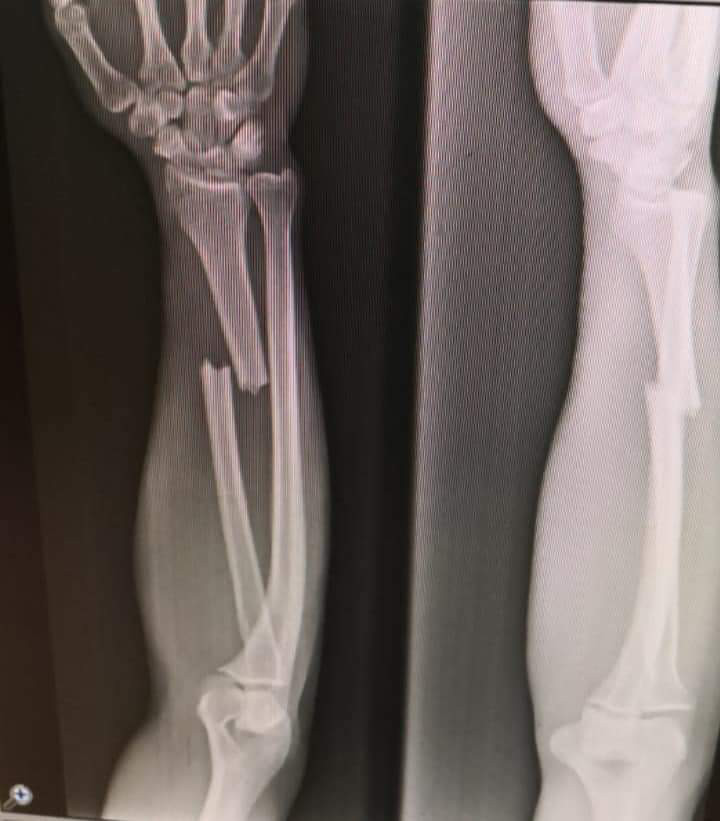

تعرض لاعب فريق النجمة ماهر صبرا لإصابة خلال تمارين المنتخب في تركيا، حيث أظهرت الفحوصات الأولية وجود كسر في يده.